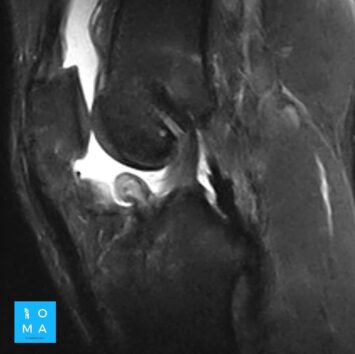

En la evaluación con medio de contraste, se evalúa la relación arterial y de las venas, esto puede servir para buscar la arteria central relacionada con la hiperplasia nodular focal o bien, para evaluar la relación con las estructuras vasculares que son muy importantes para el planeamiento quirúrgico .

en este caso, aún cuando los hallazgos son atípicos tanto para hiperplasia nodular focal como para adenoma, nos inclinamos hacia el diagnóstico de adenoma debido a los antecedentes de la paciente, el tamaño de la lesión, el área de sangrado, el contenido de grasa.